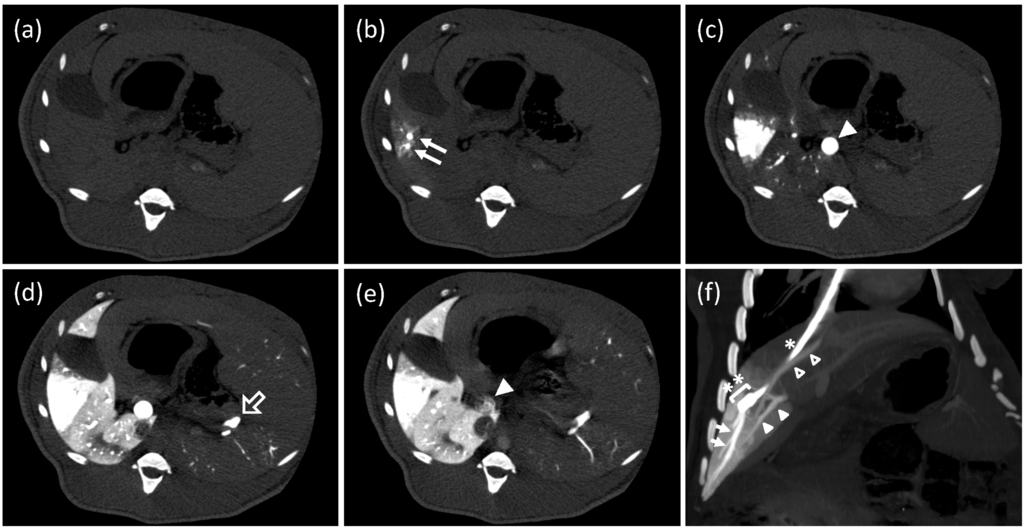

3.2. Single-Level Computed Tomography

3.3. Conventional Enhanced Computed Tomography